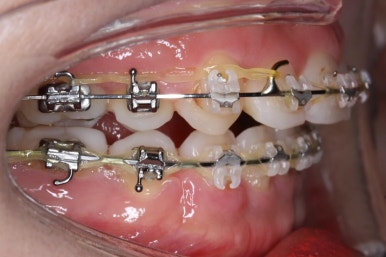

입안 모습입니다.

윗니와 아랫니 모두 각각 보면 가지런해 보이며 발치를 했던 자리도 거의 다 메워져서 양호해 보입니다. 훑어 보면 굳이 더 교정을 해야할 부분이 있을까? 싶겠지만 다음 사진을 보면 알 수 있습니다.

입 속 좌우 모습인데요. 문제점은 다음과 같이 있었어요.

윗니와 아랫니의 교합이 톱니바퀴처럼 맞물리지 않고 1대1 정면으로 맞닿고 있었습니다.

앞니쪽도 보면 윗니와 아랫니의 앞뒤 간격이 크게 차이나는 것을 볼 수 있습니다.

발치교정을 하였을 때, 흔히 나타나는 문제인데 앞니의 각도가 안으로 매우 굽어져 있습니다. 옥니라고 하며 발치를 한 공간을 너무 당겨 넣다보면 발생할 수 있습니다.